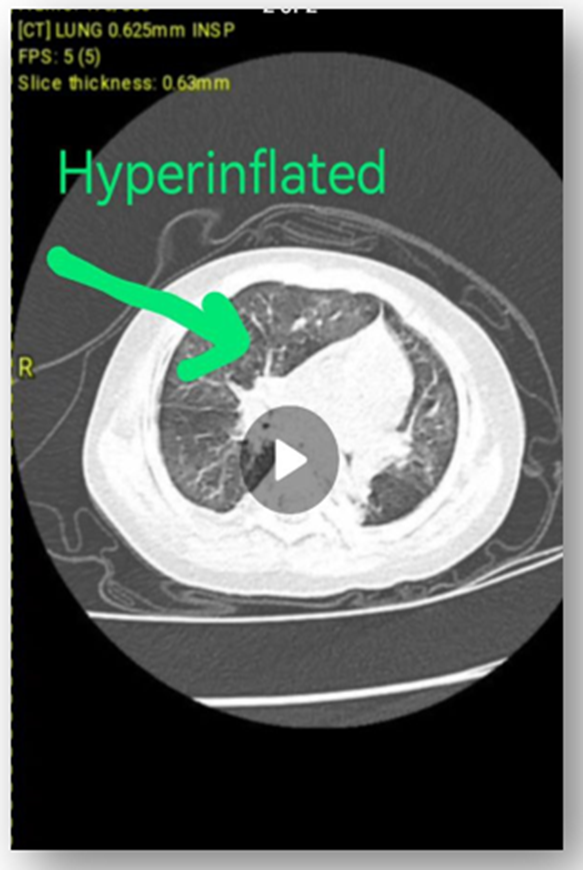

Contrast Enhanced Chest CT Scan: (figure 2)

No strong evidence of infectious process, no sign of interstitial lung disease, no bronchial thickening of bronchiectasis seen, no evidence of mediastinal or hilar lymphadenopathy, no evidence of pleural or pericardial effusion, no evidence of intraluminal obstructive lesion, no sequestration, no CPAM or bronchogenic cyst, heart shows normal size and shape.

Right upper lobe anterior and apical segment hyperinflation + collapsed right upper lobe posterior segment and bibasilar medial segment could suggest Congenital Lobar Over inflation